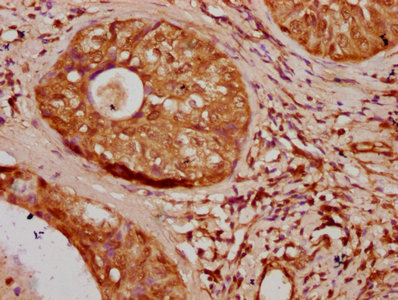

• IHC image of CSB-PA010379OA106nbhbHU diluted at 1:20 and staining in paraffin-embedded human cervical cancer performed on a Leica BondTM system. After dewaxing and hydration, antigen retrieval was mediated by high pressure in a citrate buffer (pH 6.0). Section was blocked with 10% normal goat serum 30min at RT. Then primary antibody (1% BSA) was incubated at 4°C overnight. The primary is detected by a biotinylated secondary antibody and visualized using an HRP conjugated SP system.